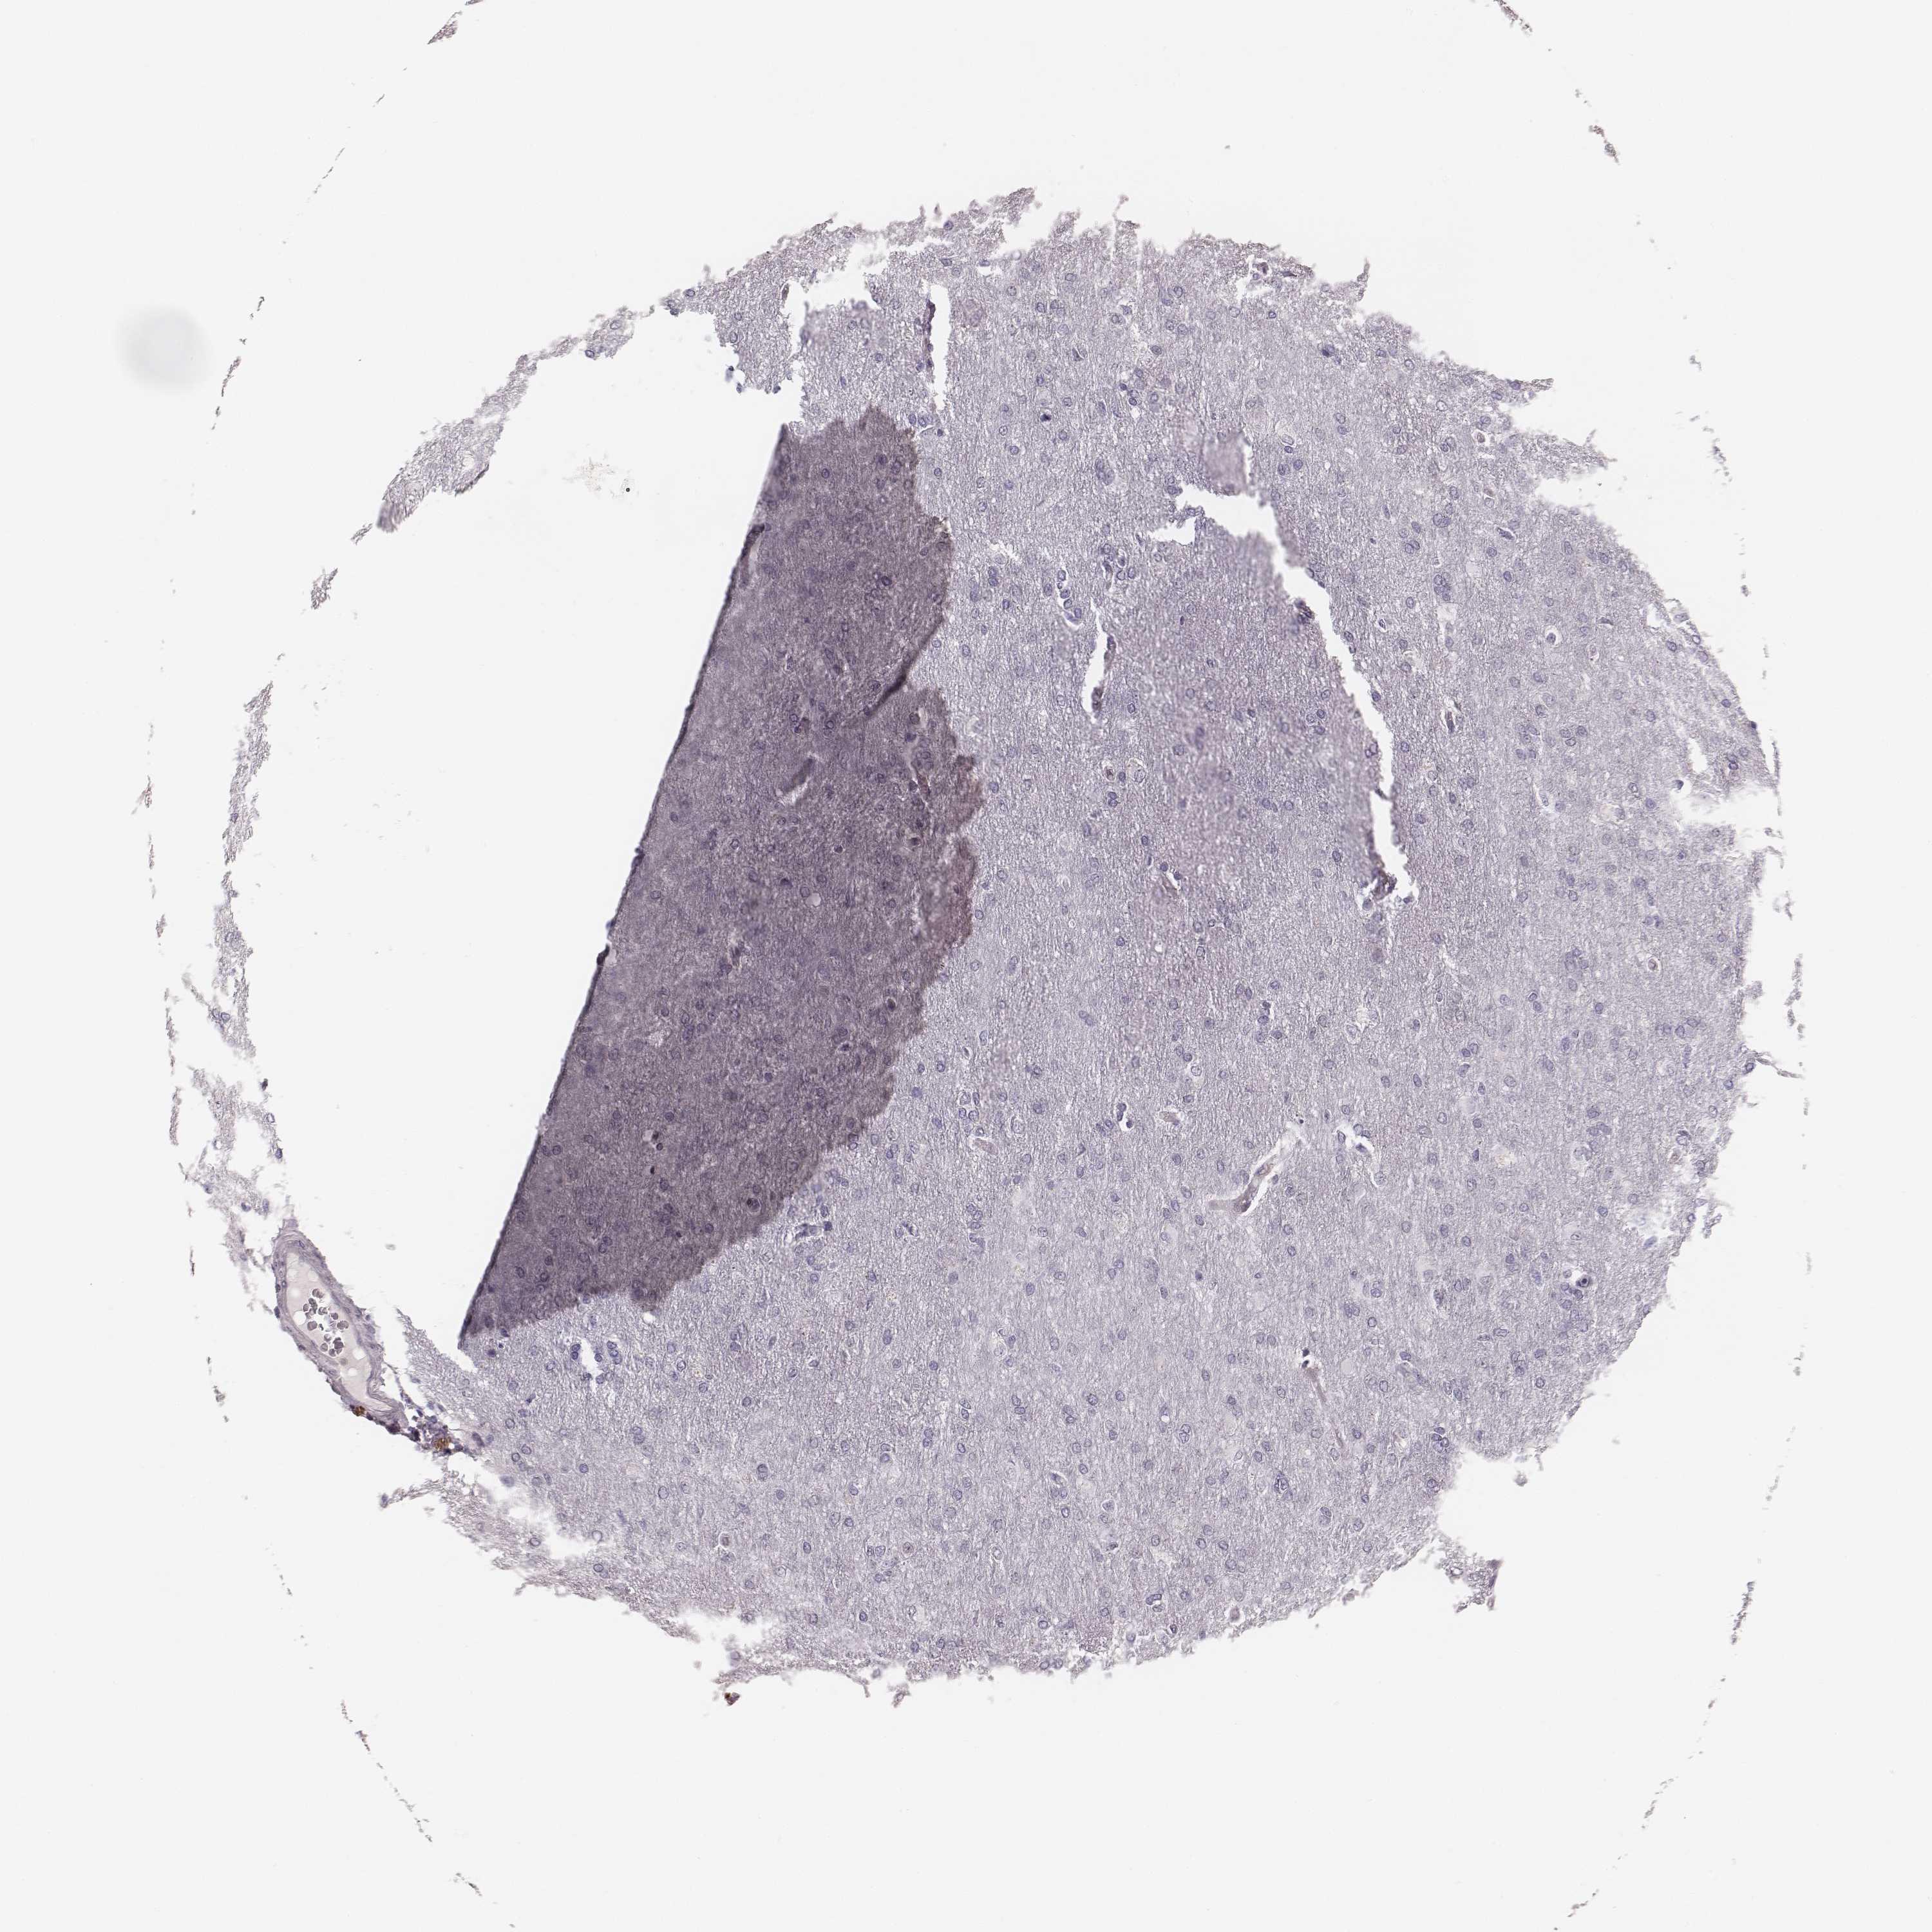

GLIOMA - Protein expressioni

A mouse-over function shows sample information and annotation data. Click on an image to view it in a full screen mode. Samples can be filtered based on level of antibody staining by selecting one or several of the following categories: high, medium, low and not detected. The assay and annotation is described here.

Note that samples used for immunohistochemistry by the Human Protein Atlas do not correspond to samples in the TCGA dataset.

Antibody stainingi

Antibody staining in the annotated cell types in the current human tissue is reported as not detected, low, medium, or high, based on conventional immunohistochemistry profiling in selected tissues. This score is based on the combination of the staining intensity and fraction of stained cells.

Each image is clickable and will lead to virtual microscopy that enables deeper exploration of all samples and also displays staining intensity scores, fraction scores and subcellular localization as well as patient and tissue information for each sample.

Antibody HPA051929

Staining

High

Medium

Low

Not detected

Intensity

Strong

Moderate

Weak

Negative

Quantity

>75%

75%-25%

<25%

None

Location

Nuclear

Cytoplasmic/membranous

Cytoplasmic/membranous,nuclear

Glioma, malignant, Low grade

Glioma, malignant, High grade

Glioma, malignant, NOS